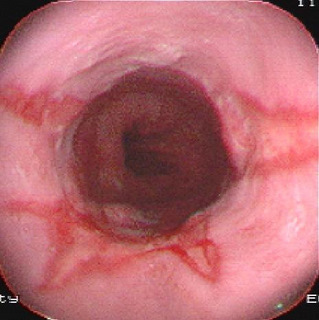

食管癌是常見的消化道腫瘤,全世界每年約有30萬人死于食管癌。其發(fā)病率和死亡率各國差異很大。我國是世界上食管癌高發(fā)地區(qū)之一,每年平均病死約15萬人。男多于女,發(fā)病年齡多在40歲以上...